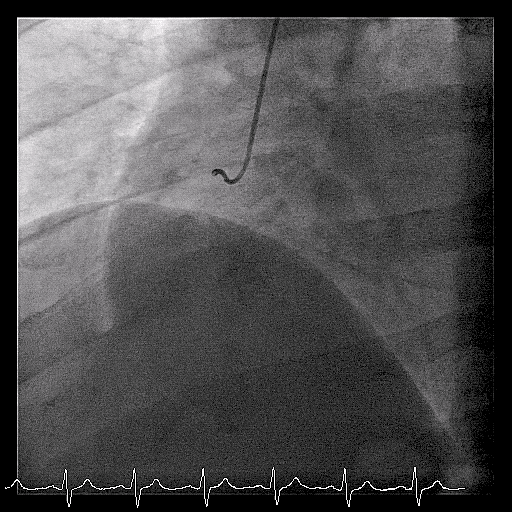

Example 1: Anomalous Left Main (Subpulmonic/Transeptal)

Note the long left main coming off the right coronary artery. Straight trajectory of the left coronary from right to left is typical of interarterial course. CT suspected subpulmonic/transeptal course and OR confirmed LM travelling between the aorta and pulmonary artery with an intramural course.